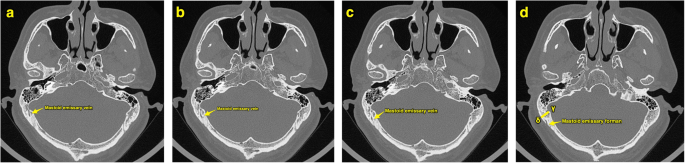

The course of mastoid emissary vein and slice B. The course of mastoid emissary vein can be traced through the continuous CT images (a–c). The slice B (d) should reveal the mastoid emissary foramen and the locations of point γ and point δ. The distance between point δ and the mastoid emissary foramen should be measured